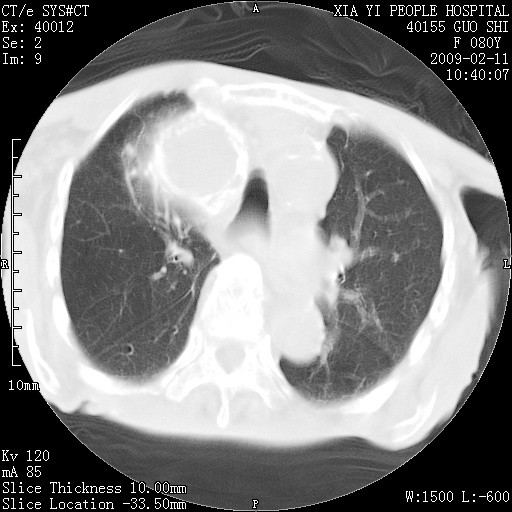

以下是引用随光逐影在2009-2-16 16:34:00的发言:[br]1)考虑右前纵隔皮样囊肿。2)双侧少量胸腔积液。

以下是引用zjzjr在2009-2-16 17:30:00的发言:[br]支持囊性畸胎瘤 双侧少量胸腔积液。